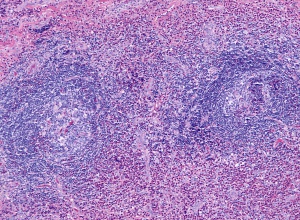

The subcutaneous lesions of Kimura’s disease are characterized by follicular hyperplasia with active germinal centers, as well as a proliferation of capillary and arteriolar vasculature, surrounded by concentric rings of reactive fibrosis composed of collagen and hyaline.[1][2][6] The follicles present in Kimura’s disease are usually well-formed, but tend to undergo degradation once infiltrated by eosinophils, at which point follicular capillary vascularization and eosinophilic microabscesses are commonly observed.[6] The vasculature present in Kimura’s disease is primarily composed of capillaries and arterioles with delicate walls and flat or cuboidal endothelium with typical nuclei.[6] The interfollicular zones are populated by numerous lymphocytes with prominent eosinophilia, although plasma cells and mast cells are also present.[6] In advanced Kimura’s disease affecting glandular tissues, normal glandular tissue is destroyed and replaced with fibrotic tissue and lymphocytic infiltrate.[6]